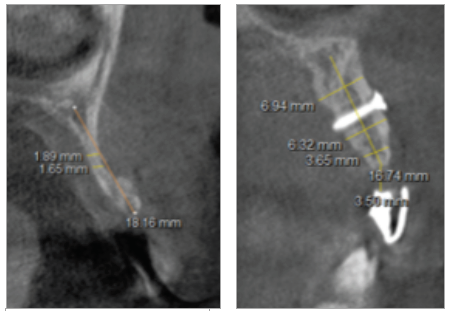

Paciente de sexo masculino de 24 años de edad, de raza mestiza, sin antecedentes sistémicos y oclusalmente estable, que fue transferido al servicio de Rehabilitación Oral del Posgrado y Especialización de la Universidad Peruana Cayetano Heredia, Lima, Perú. Recibió previamente tratamiento ortodóncico en el servicio de Ortodoncia y Ortopedia Maxilar por 6 años. Al examen intraoral presentó agenesia de las piezas 12 y 22 con evidencia de defectos óseos, presenta fenotipo periodontal grueso (figura 1). Al examen radiográfico se observa disminución generalizada de las raíces (Rizomicri), presenta ensanchamiento del ligamento periodontal generalizado (figura 2). Para el plan de trabajo para el diagnóstico se obtuvieron modelos de estudio primario, realizando el encerado para la planificación del tratamiento del sector anterosuperior. Al análisis tomográfico se evidenció poca disponibilidad ósea, motivo por el cual se planificó dos injertos en bloque de mentón con hueso particulado y plasma rico en plaquetas previo a la colocación de implantes dentales (figura 3 y figura 4). Pasado el tiempo de osteointegración (6 meses) se colocaron dos implantes Strong WS Cono Morse (SIN®, Sao Paulo, Brasil) de 3.5 mm x 11 mm. En la segunda fase, se confeccionaron provisionales de acrilico termocurado Vitalloy® (Vitacryl; A. Tarrillo Barba S.A., Lima, Perú) para el manejo de los tejidos blandos a nivel de las piezas 12 y 22, los cuales estuvieron fijados a un cilindro provisional de titanio (SIN®, Sao Paulo, Brasil) atornillado al implante, verificando la adaptación de este al implante mediante una radiografía periapical (figura 5). El cilindro fue recortado dando una altura de 6 mm, los provisionales fueron agujerados en el medio (figura 6), de tal forma que el cilindro calce en el medio del espacio edéntulo, se cubrió la entrada del cilindro con teflón (Golfo USA®) y se capturó el cilindro con acrílico de autocurado Duralay color 62 (Reliance Dental Manufacturing LLC, Illinois USA) (figura 7). Después del acrilizado se retiró el provisional, en la parte cervical se realizó un incrementó con resina fluida (Filtek™ Z350XT Flow - 3M ESPE Dental Products. St. Paul, Minnesota, USA) formando el contorno crítico a 2mm por debajo del zenit de los incisivos centrales de tal manera que entre los zenits de los incisivos centrales, laterales y caninos formen una zona triangular. El contorno subcrítico se realizó de forma convexa (figura 7 y figura 8). Se finalizó con el acabado y pulido del provisional con gomas de grano grueso (gris) y grano fino (verde) (Politip, Ivoclar-Vivadent; Schaan, Liechtenstein). Se manejó la conformación de los tejidos blandos en 2 citas mediante la adición por capas de resina compuesta (Filtek™ Z350 - 3M ESPE Dental Products. St. Paul, Minnesota, USA) a nivel del contorno crítico y subcrítico a las 2 semanas y 4 semanas de la instalación del provisional (figura 9 y figura 10). Se logró conformar las papilas interdentales, el contorno crítico y subcrítico observando que los tejidos se encontraran estables, sin inflamación, con el color de la encía igual a la encía adyacente; todo esto nos indicó que se podía realizar la impresión definitiva. La instalación final se realizó con coronas metal cerámicas cementadas (figura 11 y figura 12).